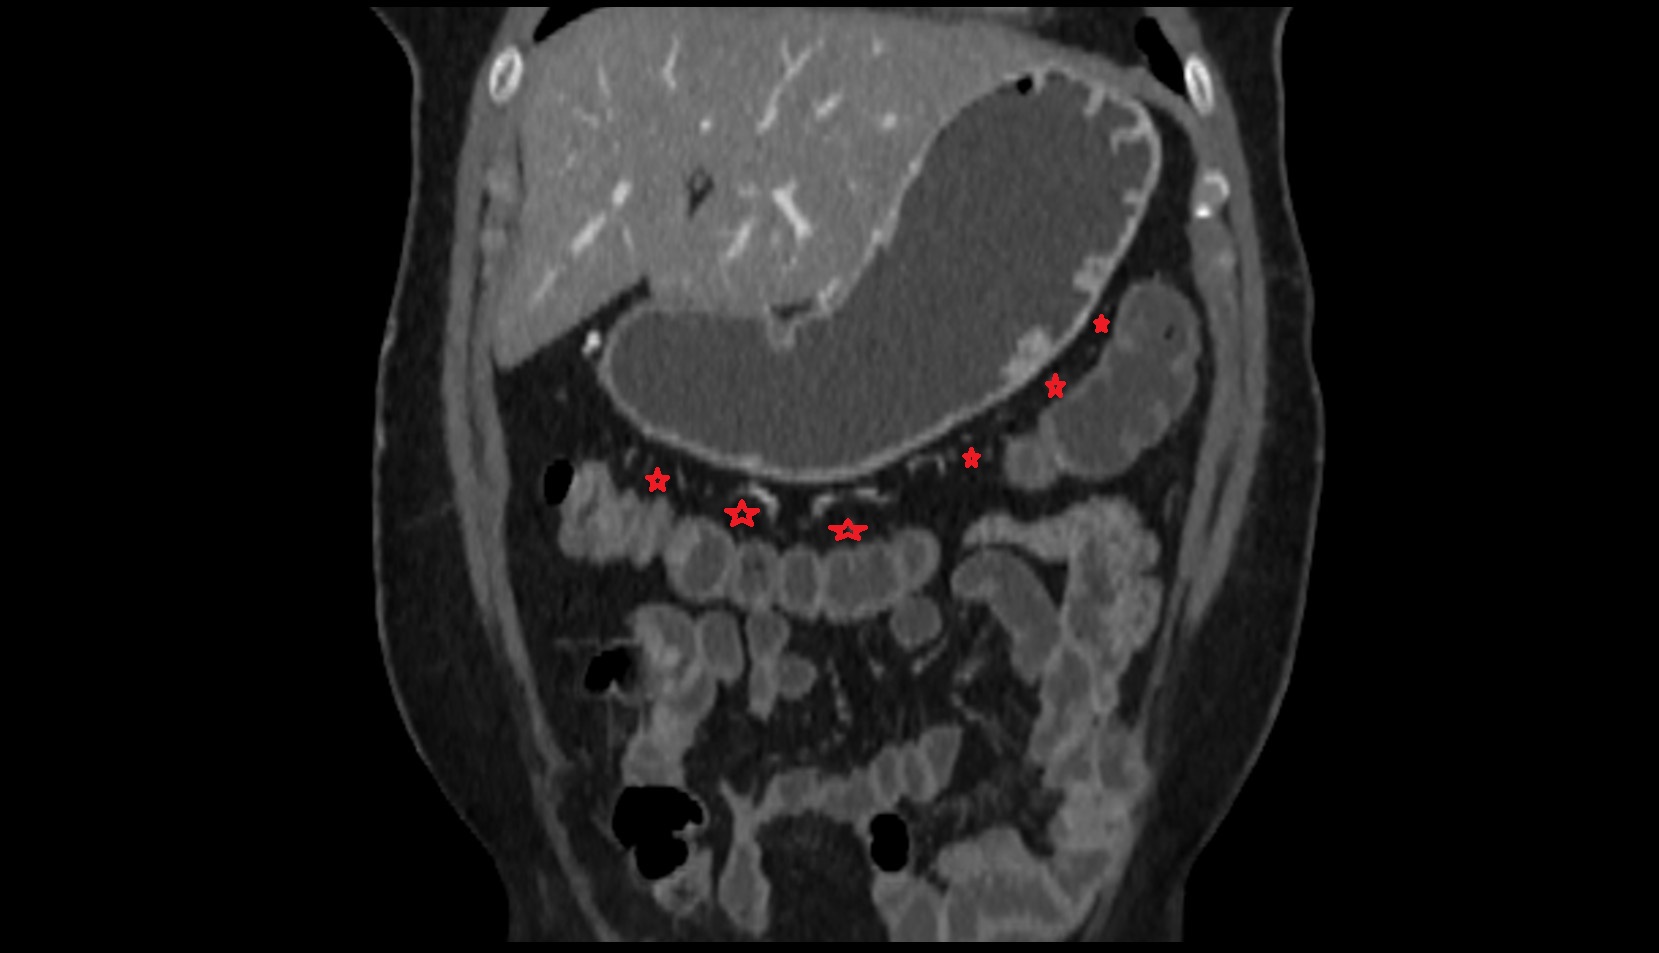

- Maternal ovaries

- Ovaries

- Right ovary

- Left ovary